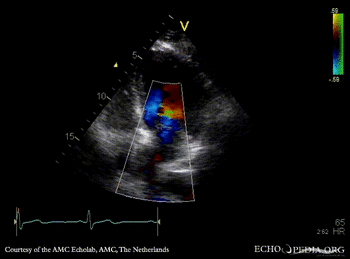

Cor triatriatum

A4CH: Color Doppler